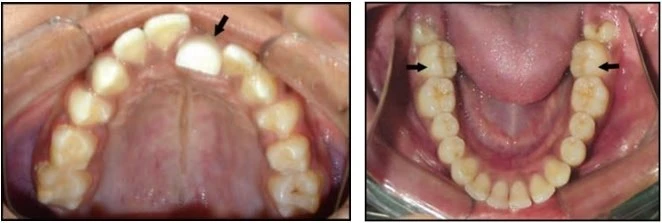

1.7 RĂNG XOAY

Đây là tình trạng những răng di chuyển xung quanh trục dọc của nó. Có hai kiểu xoay răng:

Gần trong hoặc xa ngoài

Mặt gần của răng nghiêng vào trong, hay nói cách khác mặt xa của thân răng nằm về phía ngoài so với mặt gần.

Xa trong hoặc gần ngoài

Mặt xa của răng nghiêng vào trong, hay nói cách khác mặt gần của thân răng nằm về phía ngoài so với mặt xa của nó.

Thuật ngữ này dùng để chỉ những trường hợp hai răng bị đổi chỗ cho nhau, chẳng hạn răng nanh đổi vị trí cho răng cửa bên.